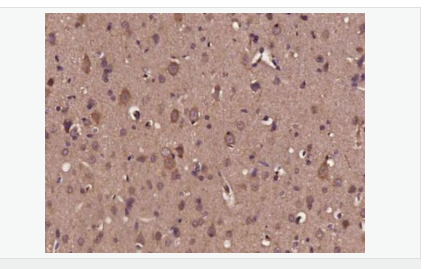

| 產品應用 | WB=1:500-2000 ELISA=1:5000-10000 IHC-P=1:100-500 IHC-F=1:100-500 Flow-Cyt=1μg/Test ICC=1:100-500 IF=1:200-800 (石蠟切片需做抗原修復) not yet tested in other applications. optimal dilutions/concentrations should be determined by the end user. |

| 產品介紹 | Neurotrophins function to regulate naturally occurring cell death of neurons during development. The prototype neurotrophin is nerve growth factor (NGF), originally discovered in the 1950s as a soluble peptide promoting the survival of, and neurite outgrowth from, sympathetic ganglia. More recently, three additional structurally homologous neurotrophic factors have been identified. These include brain-derived neurotrophic factor (BDNF), neurotrophin-3 (NT-3) and neurotrophin-4 (NT-4), also designated NT-5. These various neurotrophins stimulate the in vitro survival of distinct but partially overlapping populations of neurons. The Trk A receptor is the preferential receptor for NGF, but also binds NT-3 and NT-4. The Trk B receptor binds equally well to both BDNF and NT-4 and to a lesser extent NT-3, while the Trk C receptor only binds NT-3. BDNF promotes the survival of neuronal populations that are all located either in the central nervous system or directly connected to it. Belongs to the NGF-beta family. Function: During development, promotes the survival and differentiation of selected neuronal populations of the peripheral and central nervous systems. Participates in axonal growth, pathfinding and in the modulation of dendritic growth and morphology. Major regulator of synaptic transmission and plasticity at adult synapses in many regions of the CNS. The versatility of BDNF is emphasized by its contribution to a range of adaptive neuronal responses including long-term potentiation (LTP), long-term depression (LTD), certain forms of short-term synaptic plasticity, as well as homeostatic regulation of intrinsic neuronal excitability. Subunit: Monomers and homodimers. Binds to NTRK2/TRKB. Subcellular Location: Secreted. Tissue Specificity: Brain. Highly expressed in hippocampus, amygdala, cerebral cortex and cerebellum. Also expressed in heart, lung, skeletal muscle, testis, prostate and placenta. Post-translational modifications: The propeptide is N-glycosylated and glycosulfated. DISEASE: Defects in BDNF are a cause of congenital central hypoventilation syndrome (CCHS) [MIM:209880]; also known as congenital failure of autonomic control or Ondine curse. CCHS is a rare disorder characterized by abnormal control of respiration in the absence of neuromuscular or lung disease, or an identifiable brain stem lesion. A deficiency in autonomic control of respiration results in inadequate or negligible ventilatory and arousal responses to hypercapnia and hypoxemia. CCHS is frequently complicated with neurocristopathies such as Hirschsprung disease that occurs in about 16% of CCHS cases. Similarity: Belongs to the NGF-beta family. SWISS: P23560 Gene ID: 627 Database links: Entrez Gene: 627 Human Entrez Gene: 12064 Mouse Omim: 113505 Human SwissProt: P23560 Human SwissProt: P21237 Mouse Unigene: 502182 Human Unigene: 1442 Mouse Unigene: 11266 Rat Important Note: This product as supplied is intended for research use only, not for use in human, therapeutic or diagnostic applications |